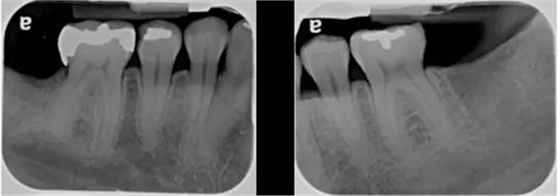

除了臨床檢查,X 光片也是必不可少的。在牙周檢查里,最常用的是根尖片和咬翼片,有時(shí)候再加上全景片。在讀根尖片前,首先要確定 X 光片的拍攝質(zhì)量,換句話說,這張根尖片有沒有用于診斷的價(jià)值。

Prichard 于 1972 年提出的判斷根尖片質(zhì)量的標(biāo)準(zhǔn):

1. 顯示磨牙牙尖,無或略顯示 牙合 面;

2. 釉質(zhì),髓腔分明;

3. 鄰面分開;

4. 除非牙位異常,牙鄰面無重疊。

圖 2 達(dá)到診斷質(zhì)量的根尖片(X 光片取自筆者治療過的病人)

圖 3 診斷質(zhì)量欠佳的根尖片(原因:牙合 面顯示太多,說明 X 光片拍攝角度有問題,片子有變形)